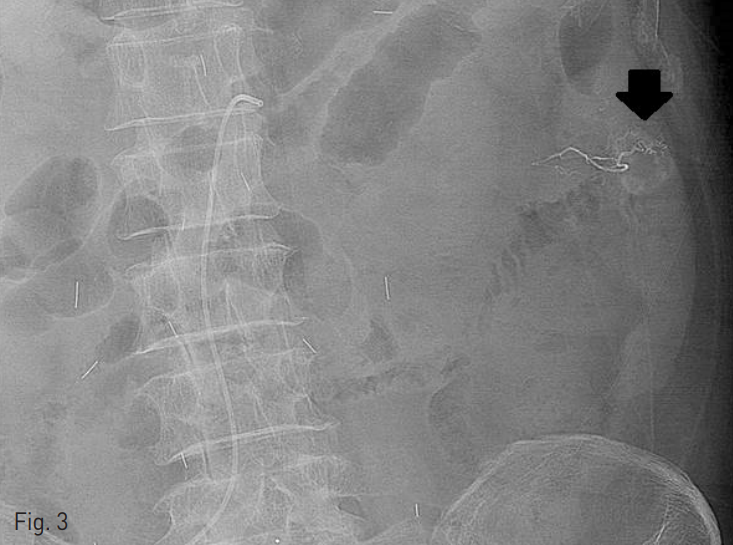

오른쪽 대퇴동맥을 통해 5 Fr 카테터 (RH, Cook, Bloomington, IN)를 삽입하여 상장간동맥 조영술을 시행하였다. 상장간동맥의 공장 가지에 약 1cm 크기의 구불구불한 모양의 늘어난 혈관이 있으면서 조기 배액되는 정맥 병변을 동반하여 혈관형성이상 병변으로 생각하였다 (Fig. 2). 이에 대해 2.0 Fr 미세카테터(Progreat, Terumo, Tokyo, Japan)를 이용하여 공장가지에 접근 하였고, 0.5cc 용량의 glue (Histoacryl, B.Braun, Tuttlingen, Germany) 1 vial을 Lipiodol (리피오돌울트라액, Guerbet, France)과 함께 1:3의 비율로 혼합하여 색전술을 시행하였다 (Fig. 3). 이후 시행한 동맥조영술에서 남아있는 병변이 없는 것을 확인하고 시술을 종료하였다.

Fig. 3

Embolization was done for jejunal angiodysplasia using glue and lipiodol (1:3).